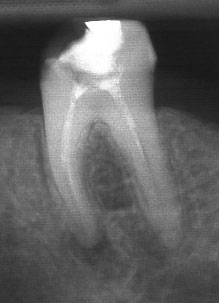

В някои случаи недобре запълненият коренов канал е показание дори за отстраняване на протезни конструкции (корони и мостове) в които е включен съответният зъб.

Винаги е необходимо лекуващият да се стреми към този резултат: